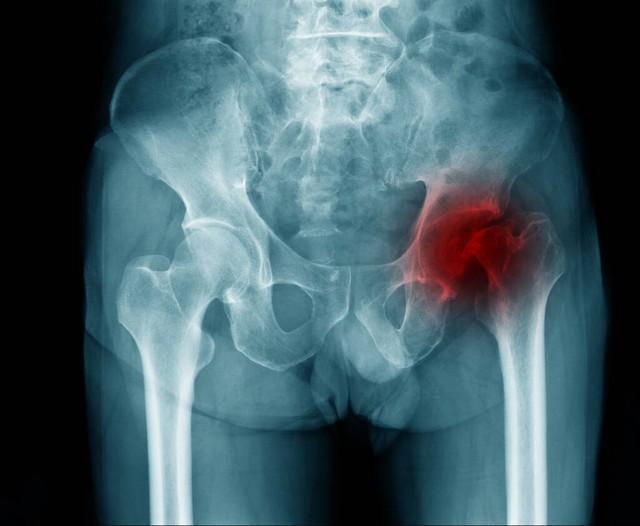

骨頭壞死是指骨組織因各種原因?qū)е卵汗?yīng)不足,從而使骨細胞死亡和骨組織破壞的過程,骨頭壞死的原因包括創(chuàng)傷、感染、長期應(yīng)用激素、骨質(zhì)疏松等,骨頭壞死后,患者可能出現(xiàn)疼痛、腫脹、活動受限等癥狀。

骨頭壞死后能否恢復(fù)取決于病情的嚴重程度、發(fā)現(xiàn)時機及治療方法,在骨頭壞死的早期階段,通過適當?shù)闹委熀涂祻?fù)措施,有可能實現(xiàn)骨組織的再生和恢復(fù),如果病情嚴重或治療不及時,可能會導(dǎo)致骨組織的不可逆損害,影響恢復(fù)。